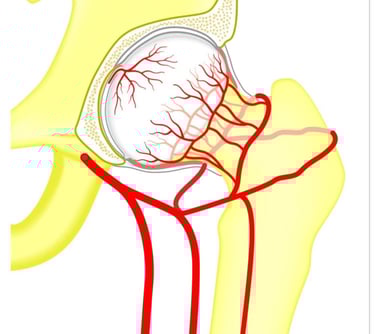

Aseptinė kaulų nekrozė – tai būklė, kai sutrinka kraujo tiekimas į kaulo audinį, dėl ko dalis kaulo pradeda irti ir mirti. Ši būklė dar vadinama avaskuline nekroze arba išeminiu kaulo pažeidimu, nes ji atsiranda be infekcijos arba bakterijų įtakos („aseptinė“ reiškia be infekcijos). Aseptinė nekrozė gali paveikti bet kurį kaulą, tačiau dažniausiai pažeidžiami klubo, kelio, peties arba riešo kaulai.

Aseptinė kaulų nekrozė atsiranda, kai nutrūksta arba sumažėja kraujo tiekimas į kaulą, o tai gali sukelti šie veiksniai:

• Traumos: kaulų lūžiai ar išnirimai gali pažeisti kraujagysles, kurios aprūpina kaulą krauju.